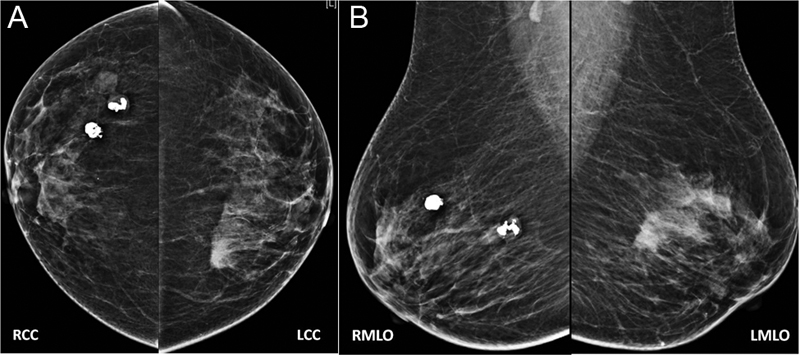

Now is the era of digital mammography, also described as full-field digital mammography (FFDM). In this technique, digital receptors are used in the place of screen film. There are manifold advantages of this technique. Digital images are incorporated with the picture archiving and communication system. They are easy to reproduce without exposing patients again to radiation, post-processing of image is possible, they can be stored for a long time without losing their quality, and can be used for comparison at a later time ([Fig. 1A] and [B]).

| Fig. 1(A and B) With Illustration 1: bilateral mammogram in CC and MLO views. It shows two popcorn calcifications in the upper outer quadrants of the right breast suggestive of involuting fibroadenomas. A high-density mass in the upper inner quadrant of the left breast is seen.

| Fig. 1(A and B) With Illustration 1: bilateral mammogram in CC and MLO views. It shows two popcorn calcifications in the upper outer quadrants of the right breast suggestive of involuting fibroadenomas. A high-density mass in the upper inner quadrant of the left breast is seen.